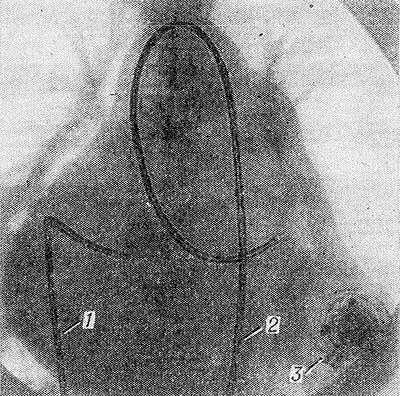

Рентгенограмма сердца с введенными в его полости катетерами (одновременная катетеризация правых и левых отделов сердца): 1 — катетер через бедренную и нижнюю полую вены проведен в правый желудочек; 2 — катетер через бедренную артерию и аорту проведен в левый желудочек; 3 — фонографический датчик (прикреплен снаружи к грудной стенке).

Венозную К. с. выполняют при исследовании правых отделов сердца и легочного ствола. Ее осуществляют с помощью инструментов для веносекции или специальным троакаром с набором канюль. Катетеры проводят через основную вену плеча, правую бедренную вену, а иногда используют подключичные вены. В некоторых случаях катетеризируют одновременно левые и правые отделы сердца (рис.).